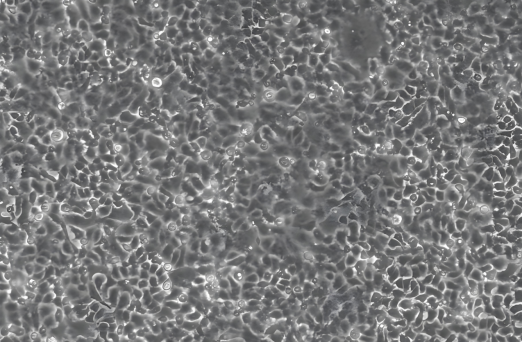

显微镜下的微生物

在食药监局的微生物检测实验中,显微镜作为核心工具,凭借其高分辨率成像、多模式观察方式,为食品安全评价、药品质量安全及微生物污染防控提供了关键技术支撑,贯穿了从形态观察到分子鉴定的全流程,其技术价值体现在以下方面:

4、病毒辅助分析:通过细胞培养观察病毒引起的细胞病变效应(CPE)。